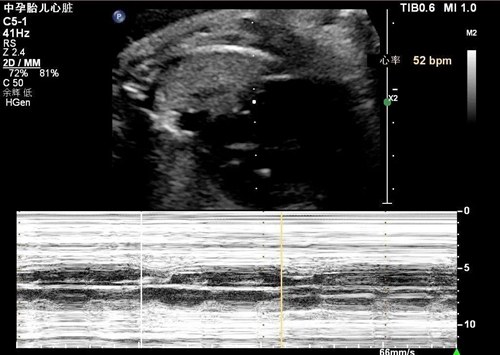

近日, 28歲的高女士(化名)在懷孕32周產(chǎn)檢時發(fā)現(xiàn)胎兒心率僅有70次/分,當?shù)蒯t(yī)院考慮為“胎兒窘迫”,被緊急轉(zhuǎn)往青島婦女兒童醫(yī)院胎兒醫(yī)學(xué)中心就診。

據(jù)了解,經(jīng)過接診醫(yī)生的仔細排查,發(fā)現(xiàn)胎兒心跳緩慢的原因不是 “胎兒窘迫”,而是一種緩慢型的心律失常——房室傳導(dǎo)阻滯。

“此類型心律失常很少在妊娠晚期發(fā)生,并且孕婦本人也沒有導(dǎo)致胎兒心律失常的常見高危因素,比如一些自身免疫性疾病”,胎兒醫(yī)學(xué)中心副主任張?zhí)@介紹道。“心電圖提示孕婦本人右束支傳導(dǎo)阻滯,雖然在成年人中比較常見,但是結(jié)合胎兒心律失常的癥狀,我們認為并非巧合”。